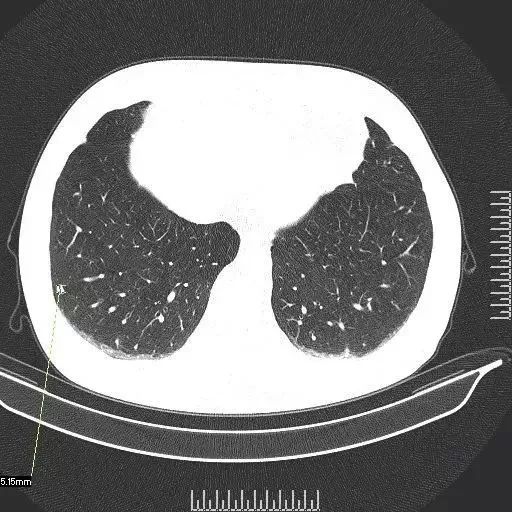

4、友谊医院影像科专家分析最全面,认为按指南应3个月随访,但患者年轻且结节位置易切除,可择期手术否认胸膜牵拉仅靠近,术后23个月可恢复正常生活手术治愈率高,无需过度焦虑人民医院主治大夫认为消炎药无法快速消退结节,考虑原位或微浸润腺癌,建议复查CT排除其他结节后证实存在3mm纯。

14、根据友谊医院预约专家CT加急你说的情况,病理比CT更准确,CT只是个影像图片,通过图片分析病变性质,而病理检查是目前的金标准可以排除肺癌发烧可能是炎性改变所致,不像是结核,因为结核CT完全能准确诊断至于呼吸困难则是病人长期吸烟致慢性支气管炎和慢性阻塞性肺气肿所致,至于休克则可能是呼吸困难所致或是其他有心脏方面。